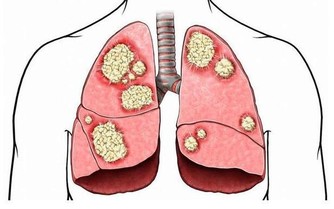

辣木籽具有天然抗凝與降脂效果,能降低血清中的膽固醇,改善血管粥樣硬化。同時能增加膽固醇的排泄,不斷清潔血管。辣木籽還會根據身體的不同狀態吃出不同的味道呢,苦意味著肝功能受損,酸則是心臟有問題,澀是脾臟功能受損,快來試試你是不是真的健康的身體吧!